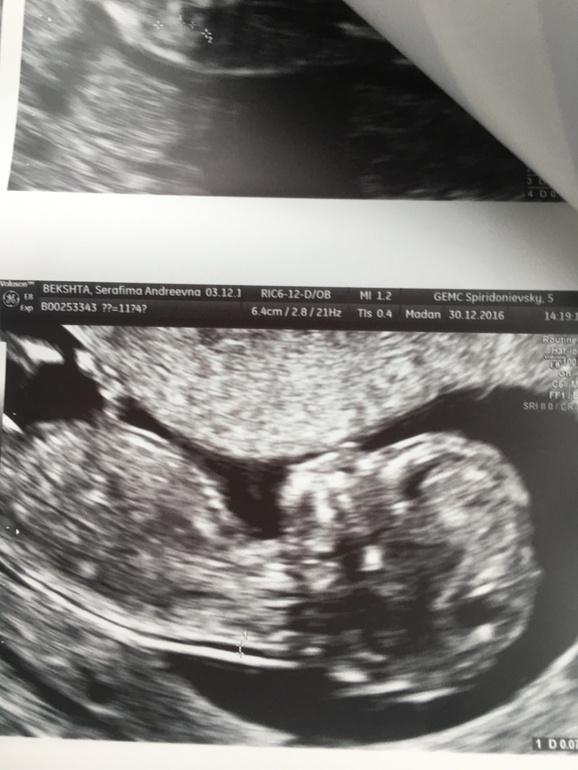

Всё о нашей беременности11+4, все все соответствует норме!

Мозг, ручки, нос кость, воротниковое пространство!я попала к чудо-доктору! Мадан Карнелия. Это благодать! Прием длился 1.20! Узи минут 30. Профессионализм видно сразу, уходили и были так ей благодарны!